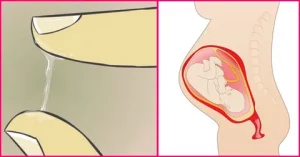

ترشحات واژن در اوایل و اواخر بارداری

از همان ابتدای بارداری ترشحات واژن بیشتر مشاهده می شود.

آیا پریود شدن در دوران بارداری ممکن است؟

در طی یک دوره، رحم پوششی را که در صورت